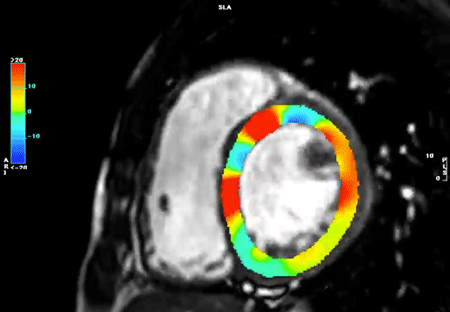

(1)strain(Figs. 11–13, Movies 2–5)

EFよりも心室の収縮能を鋭敏に反映するとされているstrainをCMRで計測可能である.左室だけでなく右室のstrainも計測可能で,最近は心房strainについての報告も出てきている.臨床的な意義についても報告が出てきており,その重要性が注目されている19).またdyssynchronyの検出にstrainを応用する試みも報告されている20)

Fig. 11 Left ventricular (LV) and right ventricular (RV) chamber quantification. For LV chamber quantification, the endocardial (red) and epicardial (green) contours are delineated in a stack of short axis slices and a 4 chamber long-axis. Counters should be marked in the round.

Fig. 12 The results of strain analysis. Top: Peak radial, circumferential, and longitudinal strains are shown in AHA 16 segments. Bottom: Each circumferential strains of basal, mid, and apical segment.

Fig. 13 Left ventricular radial strains in 3D view

strainの解析結果・方法

左室全体としての心筋ストレインをglobal strainといい,それぞれの方向でglobal circumferential strain(GCS),global radial strain(GRS),global longitudinal strain(GLS)と呼ばれる.四空長軸像や左室二腔像,短軸像などの断面像を用いて以下の方法に則って心室strainの解析を行うと,GCS,GRS,GLSがそれぞれ算出される.また,これらの断面を複数組み合わせて同時に解析を行うことで3Dでのstrain解析を行うことが可能となり,AHA 16 segment modelでの結果表示や,心室3Dモデルにカラーを載せて結果を表示することも可能となる.一例として,解析アプリケーション“CVI42”(Circle Cardiovascular Imaging, Calgary, Canada)を用いた解析結果を示す(Figs. 12, 13, Movies 2–5).